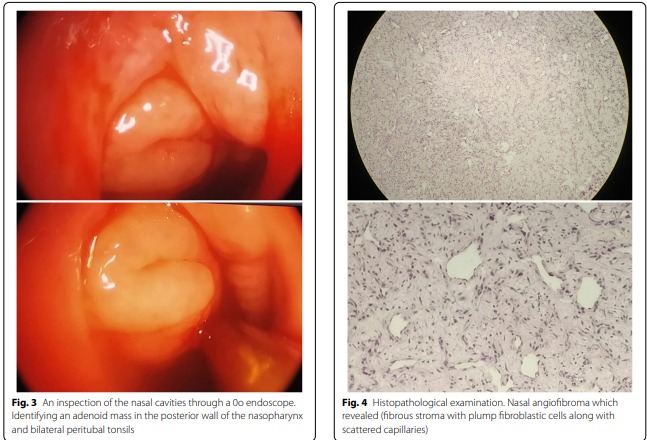

وذكرت الدكتورة يارد أن المقال البحثي تضمن مراجعة في الأدب الطبي لمثل هذه الحالات مع عرض حالة ورم وعائي ليفي لانموذجي ناشئ على حساب الوتيرة الأنفية كحالة سابعة على مستوى العالم لدى طفل بعمر 6 سنوات راجع العيادة الأذنية في مشفى المواساة الجامعي في شهر آب العام الماضي بشكوى انسداد أنف وحيد الجانب مع شخير ورعاف متقطع ومتزايد في الشدة تدريجياً من دون أي سوابق مرضية.

وأضافت الدكتورة يارد لـ “أثر” أنه بعد التقييم السريري والاستقصاءات الشعاعية أُخذ القرار بضرورة التدبير الجراحي تحت التخدير العام وبالجراحة التنظيرية النوعية واستئصل الورم ككتلة واحدة مع التمكن من السيطرة على النزف بالتخثير الكهربائي، وجاءت نتيجة التشريح المرضي مؤكدة تشخيص الورم الوعائي الليفي على حساب الوتيرة الأنفية، وبعد متابعة الطفل على مدى عام كامل بعد الجراحة لم يُلاحظ أي نكس.

وبينت الدكتورة يارد لـ “أثر” أنه نسيجياً يُعد هذا الورم شبيهاً بالورم الوعائي الليفي المتوضع في البلعوم الأنفي، وهو من الحالات الشائعة عادة والتي يصيب الذكور فقط بسن المراهقة لأسباب هرمونية، إنّما يختلف عنه سريرياً ووبائياً، مؤكدة أنه وبسبب الاختلافات تُشكل هذه الحالة السريرية تحدياً في التشخيص، وتحتاج إلى تقييم دقيق ونسبة شك عالية بوجودها للتمكّن من الوصول إلى التشخيص والتدبير الصحيحين.